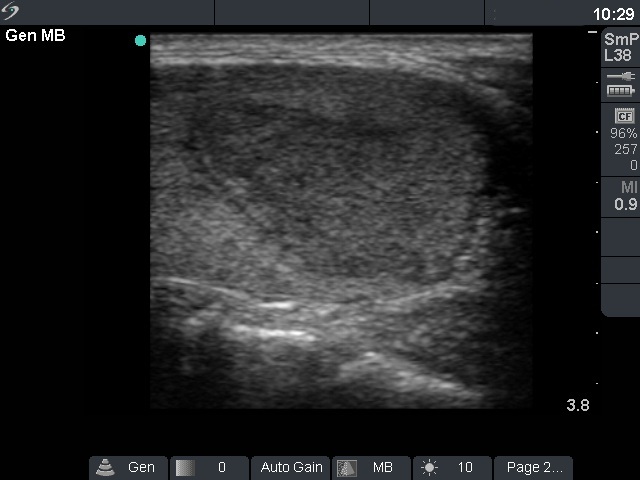

Ultrasonography: thee basic echo structure of the thyroid was normal. There was a hypoechogenic inhomogeneous nodule in the left lobe. The nodule increased in size from 12x10x16 mm to 17x12x19 mm one year after (first row of US images) and to 30x16x29 mm 3 years after the first investigation (second row of US images), i.e. from 1.0 mL to 7.3 mL. Both the perinodular and the intranodular blood flow was increased, the latter irregularly increased.